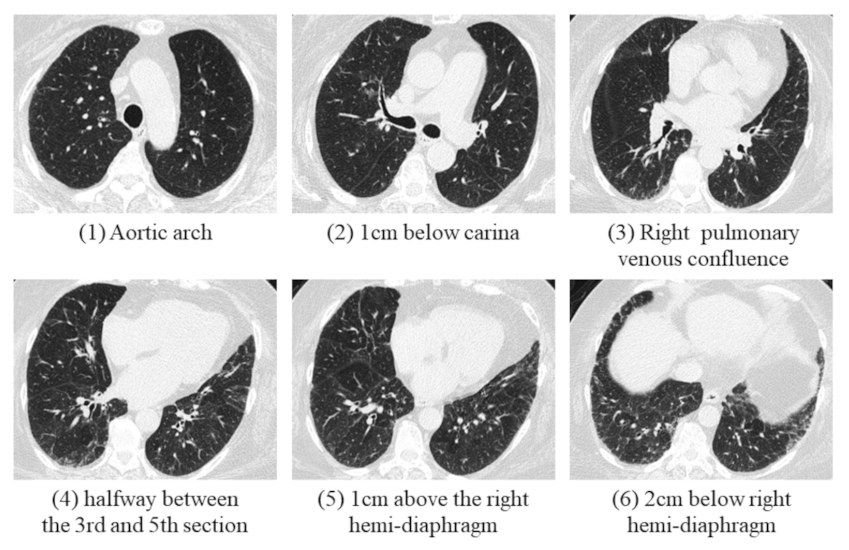

All CT images were reviewed by two radiologists (W.-M.H. and C.-H.Y.) with respectively 8 and 18 years of experience in chest CT and blinded to the clinical lung function information. The fibrotic score was obtained at six levels: (1) aortic arch, (2) 1.0 cm below the carina, (3) right pulmonary venous confluence, (4) halfway between the third and fifth section, (5) 1.0 cm above the right hemi-diaphragm, and (6) 2.0 cm below the right hemi-diaphragm (Figure 1) [18]. The proportion of content with at least one feature among honeycombing, traction bronchiectasis (TB), subpleural reticulation, or ground glass opacity with TB in each section, was scored to the nearest 5.0%, and the fibrotic score was measured as the average percentage among the above six sections [19].

Figure 1.

A 69-year-old female was diagnosed with IPF with probable UIP pattern in an MDD meeting. The percentage of fibrosis was calculated in these six levels, and the fibrotic score was calculated as the average percentage of these six sections.